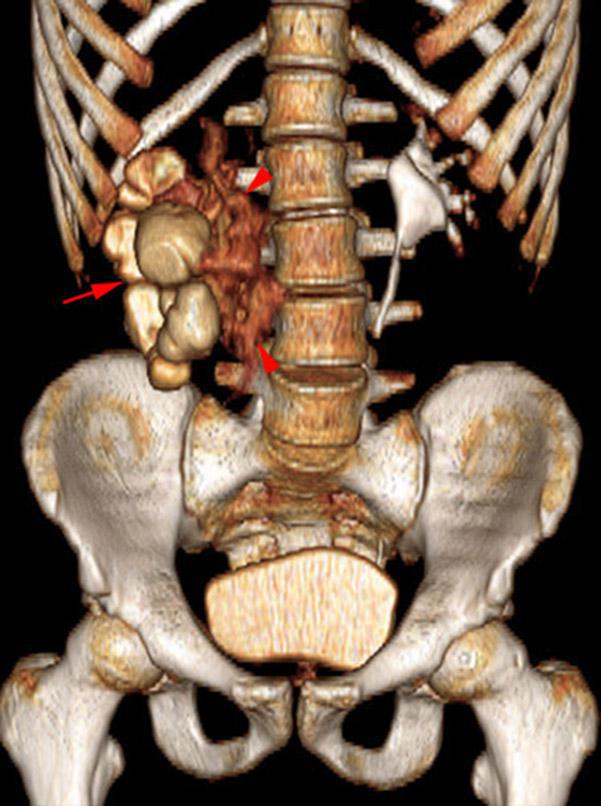

Estallido renal